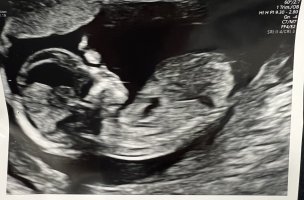

Det var i slik vinkel som bilde nr 2 her at min GY også gjetta på jente 12+3Synes ikke så godt her.. målt til 12+2 men gyn hadde en anelse ved bilde 2 der![]()

hu såg aldri etter "nub".